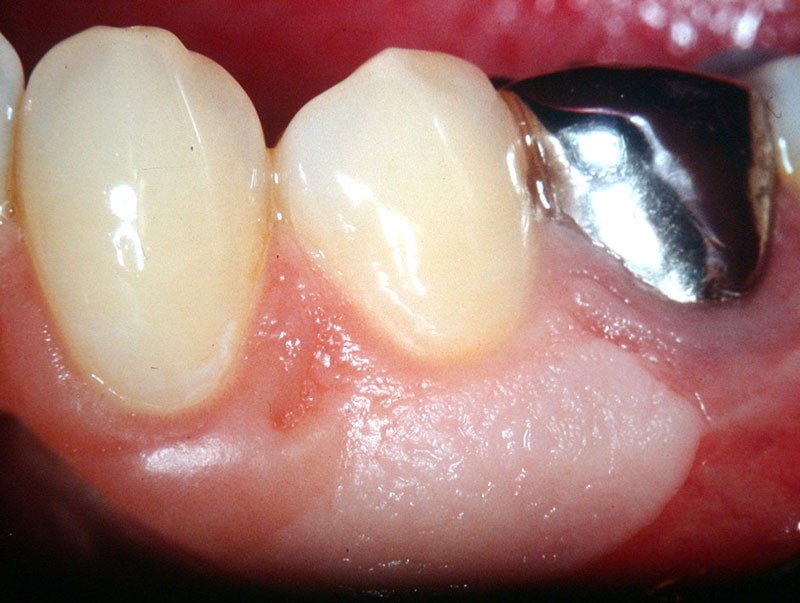

Dans ce premier cas, la présence d’un complexe muco-gingival inadéquat (fig. 1) est observée sur une canine et une prémolaire.

Cette absence de gencive attachée peut prédisposer à la formation d’une récession gingivale. Une greffe épithélio-conjonctive est réalisée. Elle permet d’obtenir un lambeau de gencive attachée kératinisée stable (fig. 2).